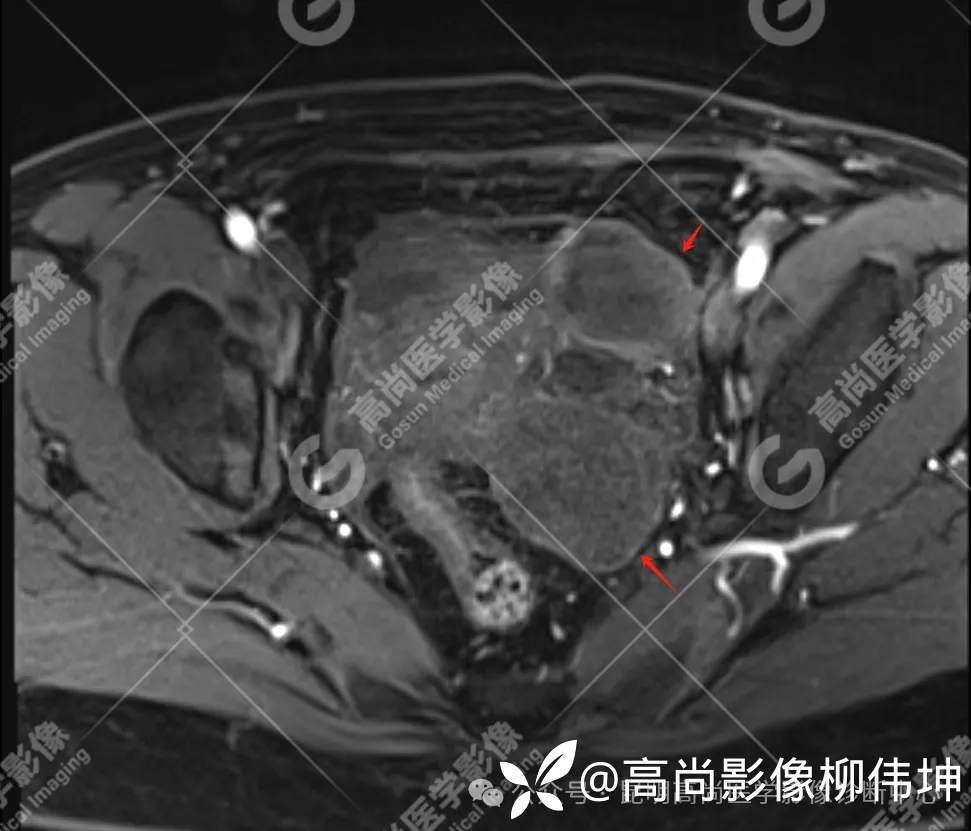

T2WI-tra

T1WI-tra

(2)MRI表现:通常双侧发生,体积巨大,呈外生性、囊实性、乳头状生长,其内见大量长T1长T2液性信号影及线性分隔,囊壁厚薄不均,可见壁结节及不同比例实性成分,呈T1等信号,T2略高信号。扩散受限,DWI呈高信号,ADC呈低信号。增强扫描实性成明显强化。另外,常可检出腹水、腹膜增厚、盆壁及盆腔脏器受累、淋巴结肿大等表现。